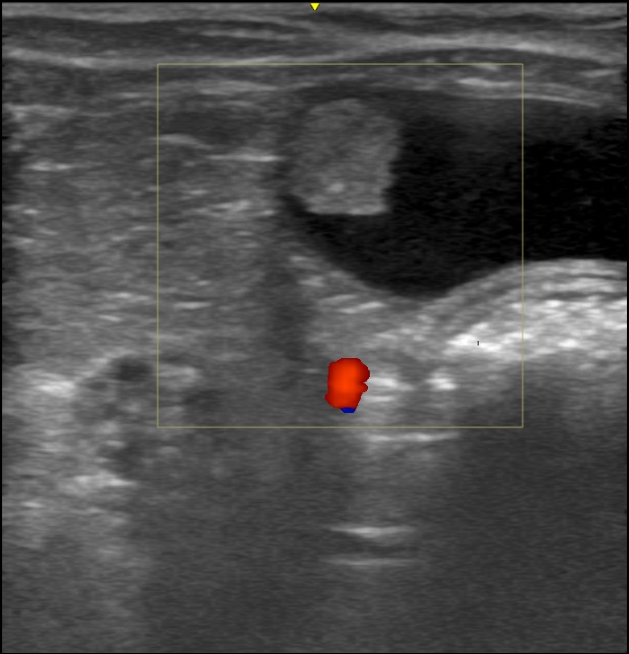

画像検査

画像検査では腎臓や膀胱などの状態を詳しく調べることができます。

レントゲン検査では腎臓や膀胱の大きさや結石の有無を確認します。

超音波検査ではレントゲン検査より詳細に、臓器の内部構造を観察可能です。

当院では、これらの画像診断を積極的に活用し、正確な診断を行なっています。

診断には、超音波検査が有効であり、膀胱内に腫瘤が見つかることが多いです。